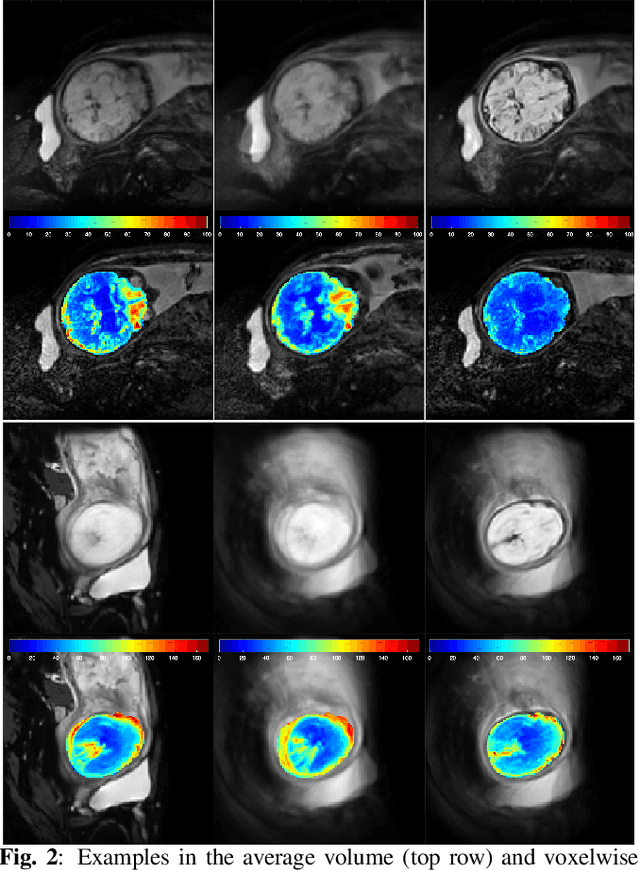

Abstract:Resting-state functional Magnetic Resonance Imaging (fMRI) is a powerful imaging technique for studying functional development of the brain in utero. However, unpredictable and excessive movement of fetuses has limited clinical application since it causes substantial signal fluctuations which can systematically alter observed patterns of functional connectivity. Previous studies have focused on the accurate estimation of the motion parameters in case of large fetal head movement and used a 3D single step interpolation approach at each timepoint to recover motion-free fMRI images. This does not guarantee that the reconstructed image corresponds to the minimum error representation of fMRI time series given the acquired data. Here, we propose a novel technique based on four dimensional iterative reconstruction of the scattered slices acquired during fetal fMRI. The accuracy of the proposed method was quantitatively evaluated on a group of real clinical fMRI fetuses. The results indicate improvements of reconstruction quality compared to the conventional 3D interpolation approach.